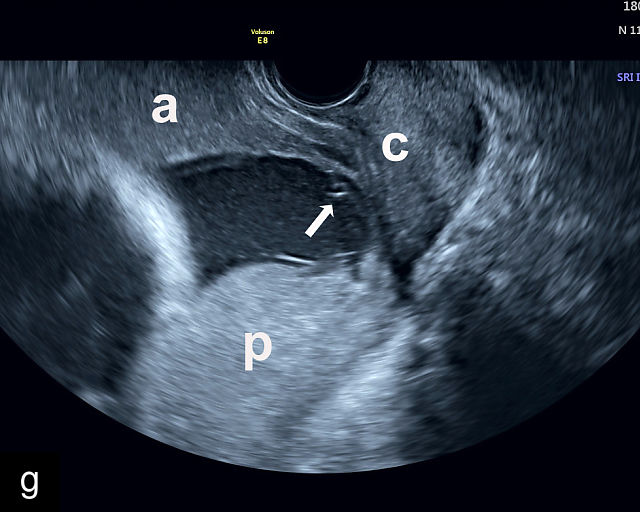

5

Placenta previa and low-lying placenta. (a) Transabdominal grayscale ultrasound image suspicious for placenta previa. The placenta (PL) appears to overlie the internal cervical os (CX). Note the time stamp: 2:19:37. (b) Transvaginal ultrasound of the same patient taken approximately 50 minutes later. Note the time stamp: 3:10:25. The internal os and the lower placental edge are both clearly seen, and the placenta does not overlie the internal os. Because the lower placental edge is 1.93 cm from the internal os, it will likely resolve by the third trimester. (c) Transabdominal grayscale ultrasound of placenta previa. The placenta (p) covers the cervix, but the cervix, especially the internal os, cannot be visualized due to shadowing. (d) Transabdominal grayscale ultrasound of placenta previa. The placenta (p) covers the cervix (c) but shadowing obscures adequate visualization. The internal os is indicated by the arrow. (e) False-positive image of placenta previa on transabdominal grayscale ultrasound. The bladder (b) is full, pushing the anterior and posterior walls of the lower uterine segment (ls) together making it appear that the placenta (p) overlies the internal os of the cervix. In reality, the line depicted by the arrowheads is where the anterior and posterior walls of the lower segment are in proximity to each other. The cervix is much lower and is obscured by shadowing (c). (f) Transabdominal grayscale ultrasound image of placenta previa. The placenta (p) covers the cervix (c), but the cervix, especially the internal os, cannot be visualized due to shadowing. b, bladder. (g) Transvaginal grayscale ultrasound image of placenta previa. The placenta (p) completely covers the internal os (arrow) of the cervix (c). The internal os can be seen clearly. h, fetal head. (h) Transvaginal grayscale ultrasound image of posterior low-lying placenta (p). The lower placental edge is clearly seen and is 1.56 cm from the internal os (arrow) of the cervix (c). The placental edge and the internal os are clearly seen. h, fetal head. (i) Transvaginal grayscale ultrasound image of a posterior placenta previa (p). The internal cervical os is clearly seen (arrow). c, cervix. (j) Transvaginal grayscale ultrasound image of an anterior placenta previa (p). The internal cervical os is clearly seen (arrow). c, cervix; h, fetal head. (k) Transvaginal grayscale ultrasound image of a posterior placenta that was thought to be low-lying on transabdominal sonography but could not be adequately assessed. This examination clearly shows the lower edge of the placenta (p) to be 2.18 cm from the internal os (arrow) of the cervix, firmly establishing that the placenta is not low-lying and allowing the patient to undergo labor safely and deliver vaginally. c, cervix. (l) Transvaginal grayscale ultrasound image of placenta previa. The placenta (p) completely covers the internal os (arrow) of the cervix (c). The internal os can be seen clearly.